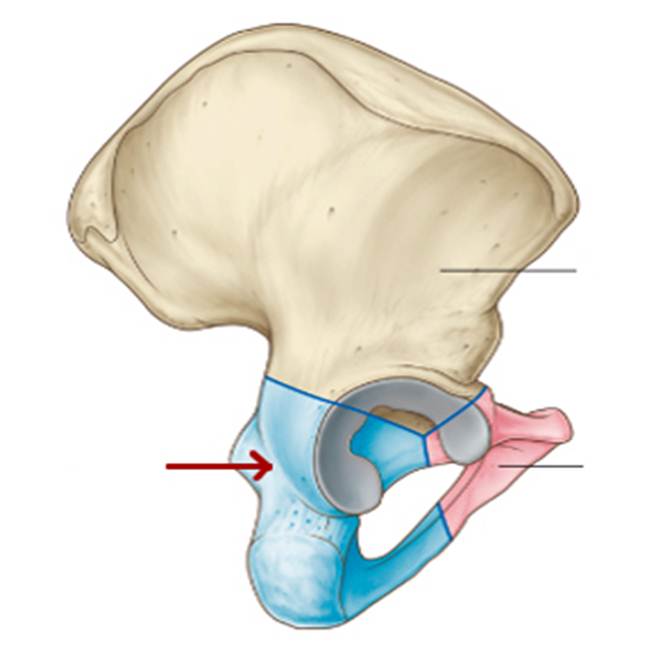

S: На рисунке обозначен art. Coxae (латинский язык).

S: Стрелка указывает на zona orbicularis

S: Стрелка указывает на lig. Ischiofemorale

S: Стрелки указывают на lig. iliofemorale

S: Стрелка указывает на lig. pubofemorale

S: Стрелка указывает на labrum acetabuli

S: Стрелка указывает на lig. Capitis femoris

S: Стрелка указывает на facies lunata